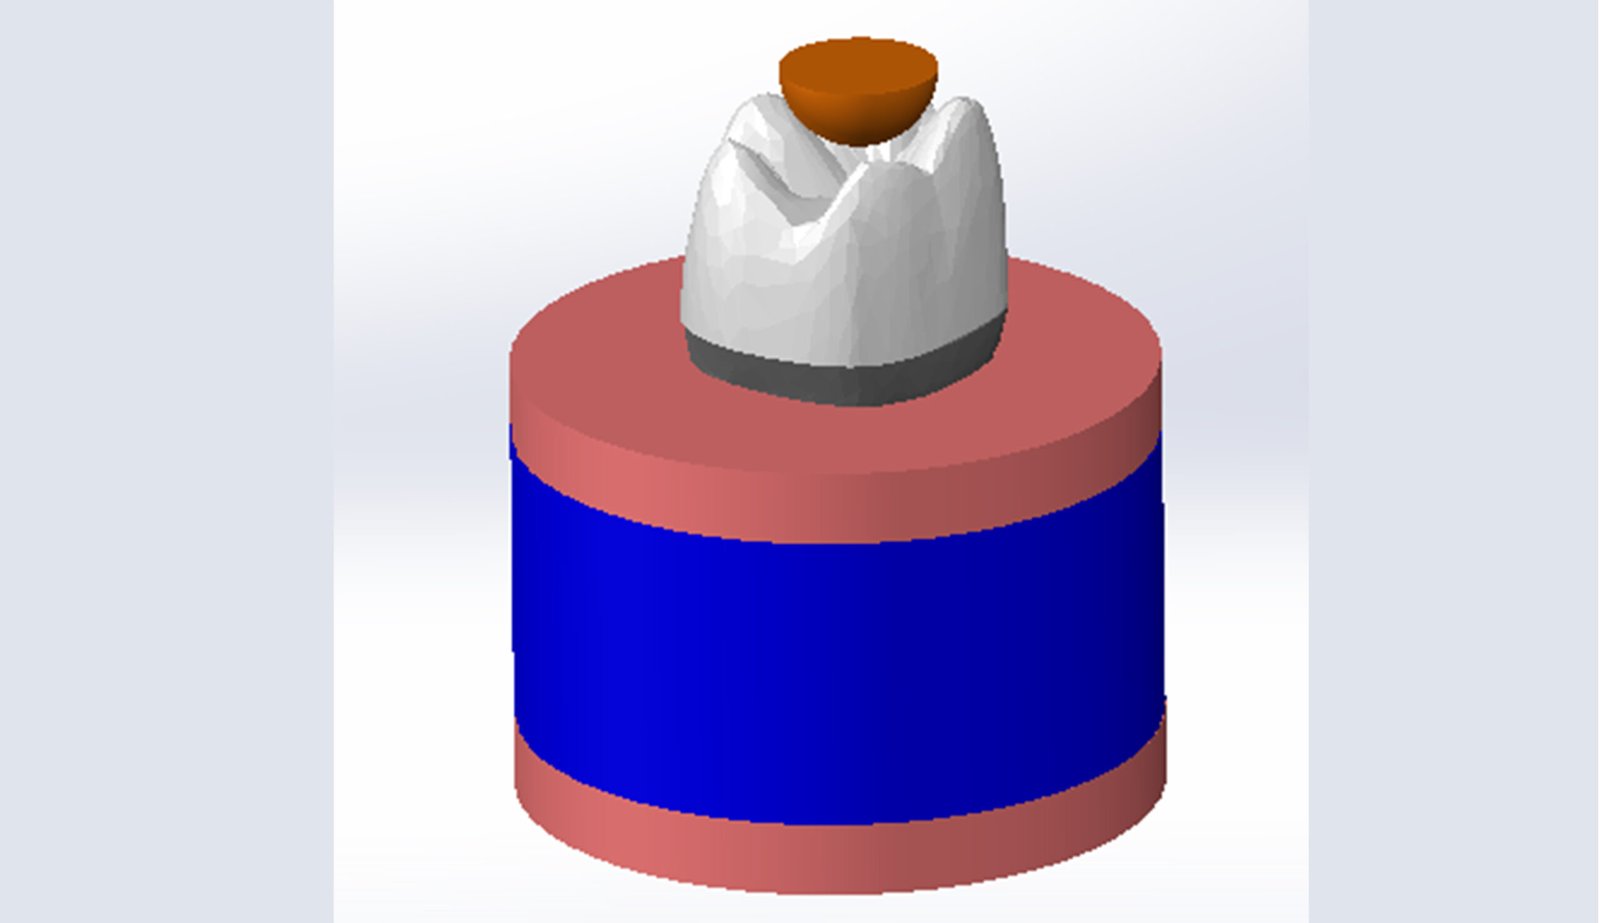

The Endodontic FEA section evaluates the biomechanical performance of root canal–treated teeth, endodontic tools, and reinforcement strategies. Through precise material characterization and micro-CT–based superimposition, we assess fracture risk, stress pathways, and instrument fatigue under various clinical scenarios. These simulations guide the selection of safer instrumentation techniques and restorative strategies. Our goal is to enhance predictability and reduce procedural complications.